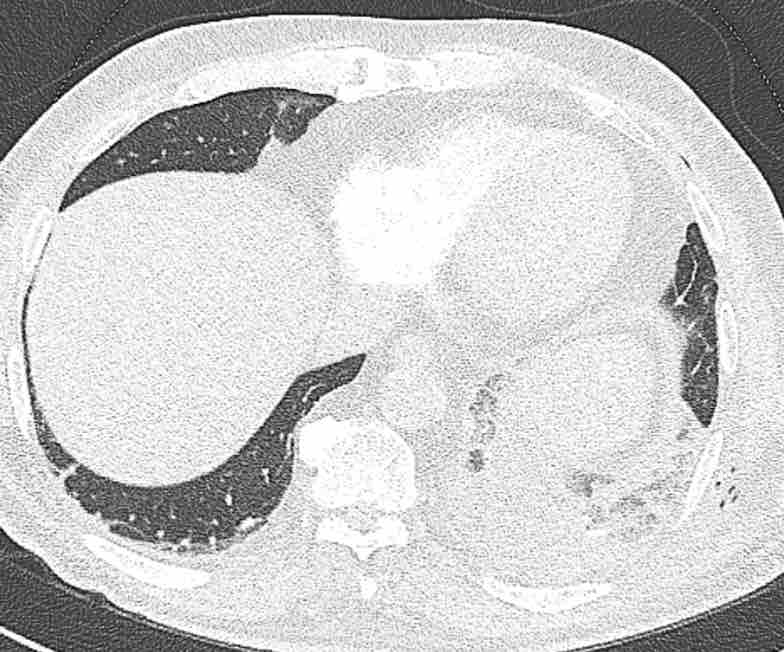

Hình ảnh

Cuộn qua các hình ảnh.

Theo dõi các phế quản của thùy dưới phổi trái cho thấy nhánh phân thùy đầu tiên của thùy dưới phổi trái còn thông; đó là phế quản phân thùy đỉnh.

Các ghim phẫu thuật nằm tại vị trí của các phân thùy đáy sau và đáy bên (LB9/10), vốn thường được cắt bỏ cùng nhau.

Do đó, phân thùy phổi có hình ảnh kính mờ và đông đặc phải là phân thùy đáy trước của thùy dưới phổi trái (LB8).

Động mạch phổi đến phân thùy này cũng không ngấm thuốc cản quang, và bản đồ tưới máu iốt nhấn mạnh thêm tình trạng nhồi máu.

Bệnh nhân đã được phẫu thuật lại và tiến hành cắt bỏ phân thùy bị nhồi máu, với xác nhận qua giải phẫu bệnh.

Trên bản đồ tưới máu iốt, có sự tưới máu ở thùy trên phổi trái và phân thùy đỉnh của thùy dưới phổi trái, nhưng không có sự tưới máu ở phân thùy đáy trước của thùy dưới phổi trái.